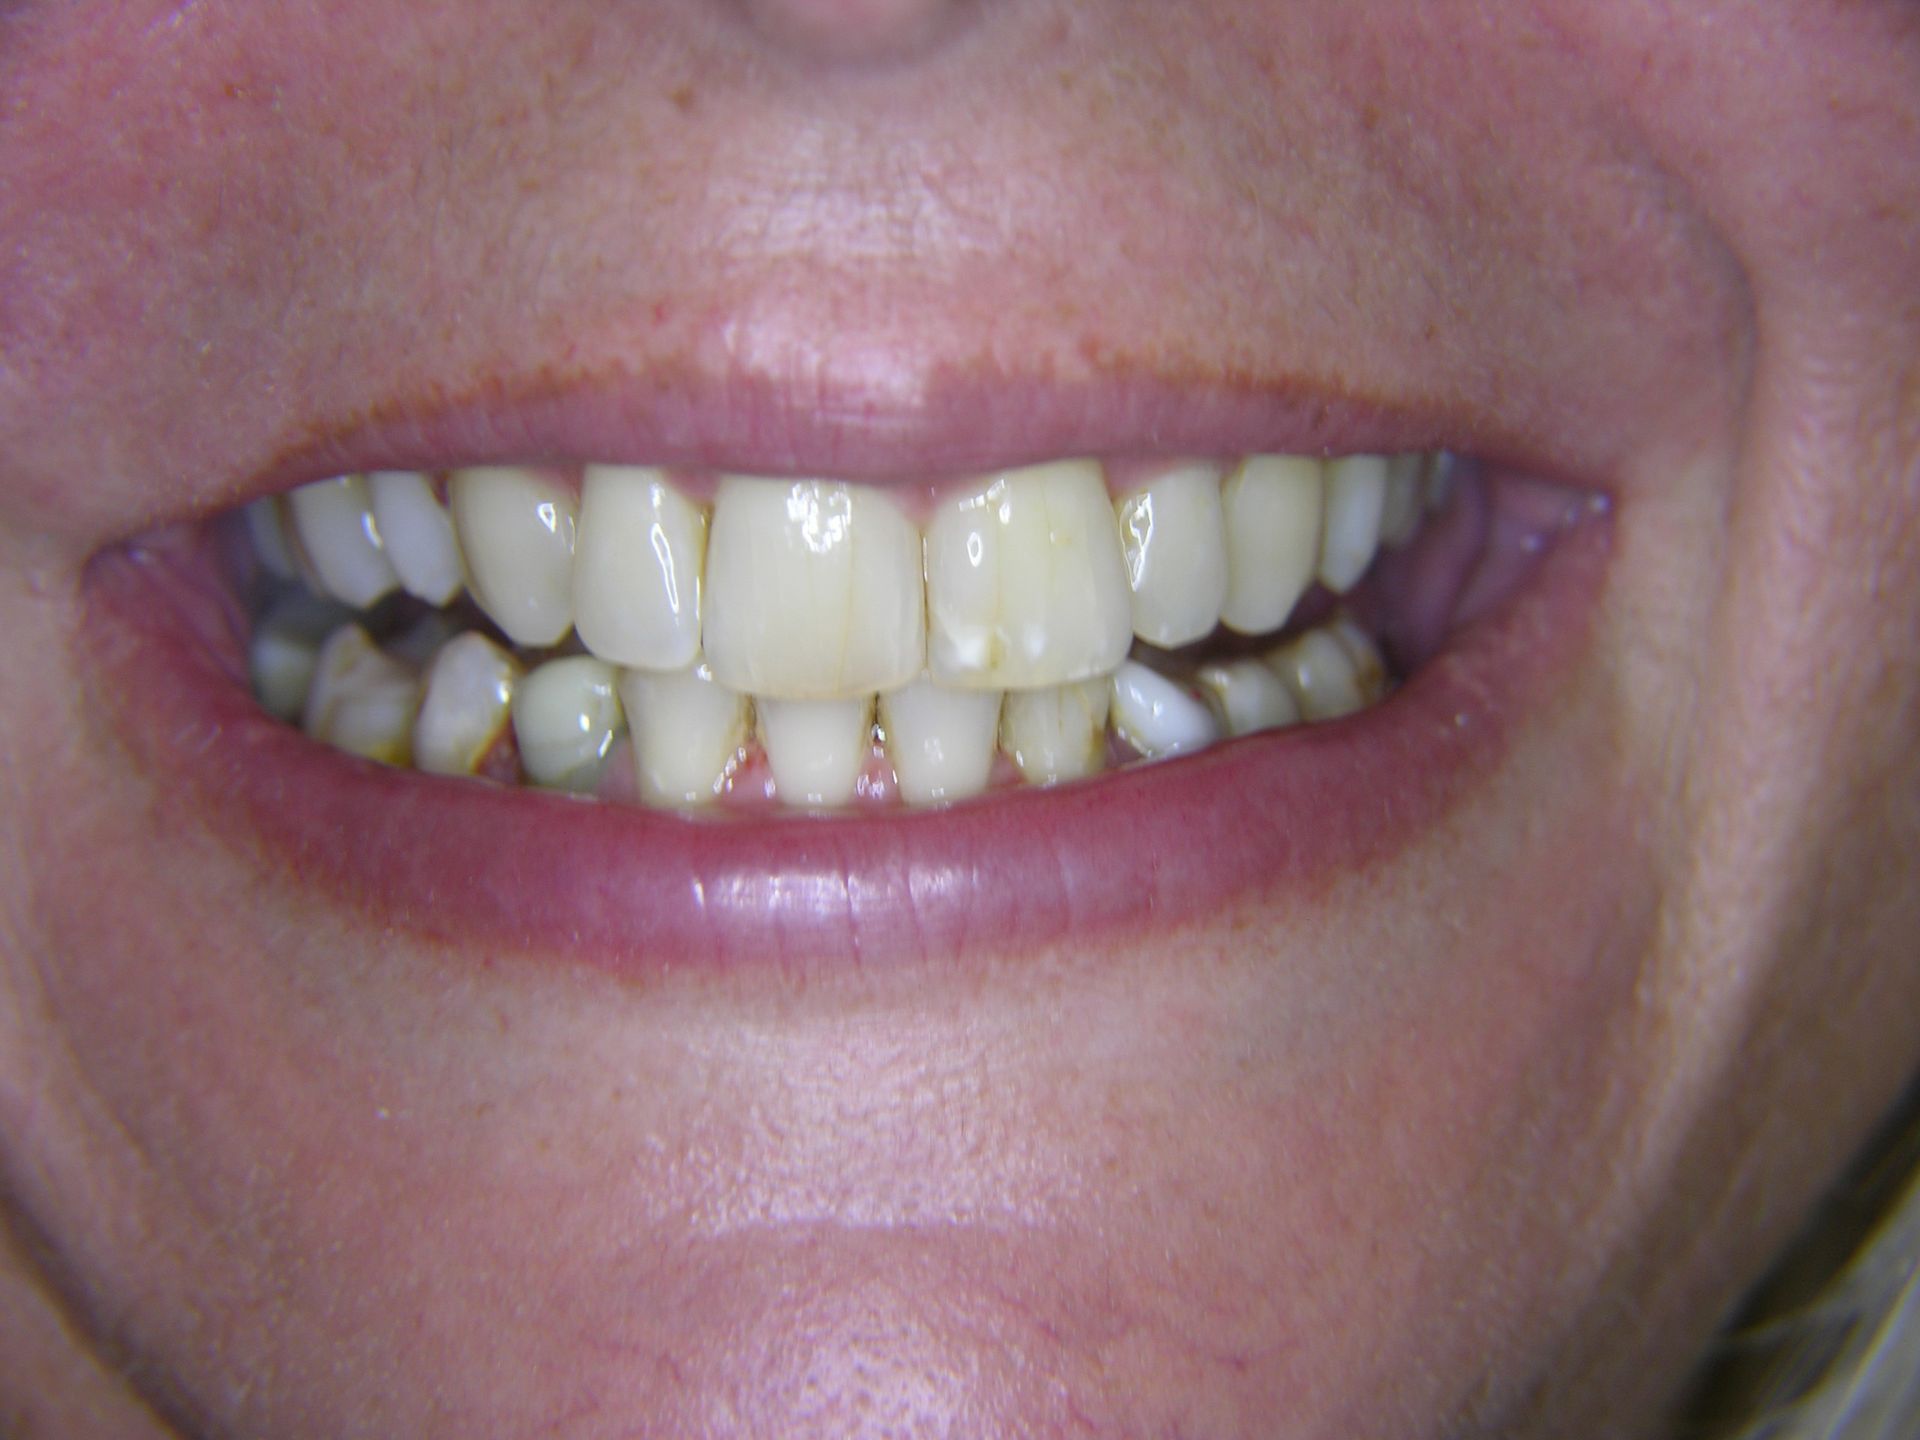

Beispiele von Versorgungen